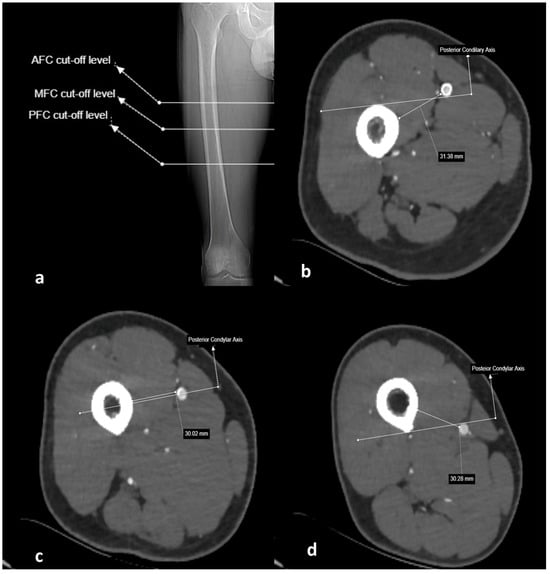

2.3. Imaging and Measurement Methods